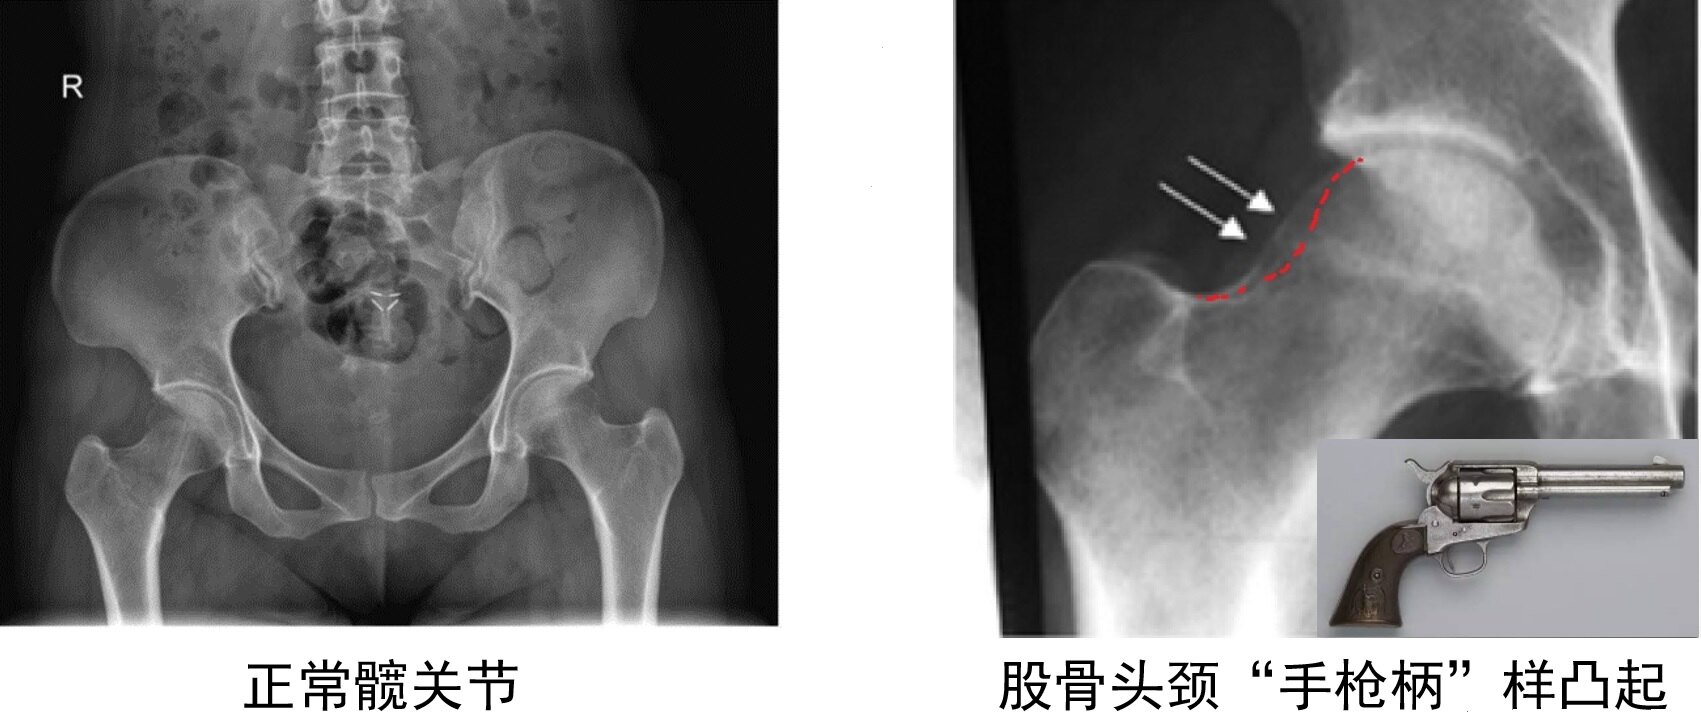

① 凸轮Cam:A. 手枪柄样畸形

图10.双髋正位X线片可看到股骨头颈“手枪柄”样隆起。

B. α角增大> 50°(45°Dunn位)